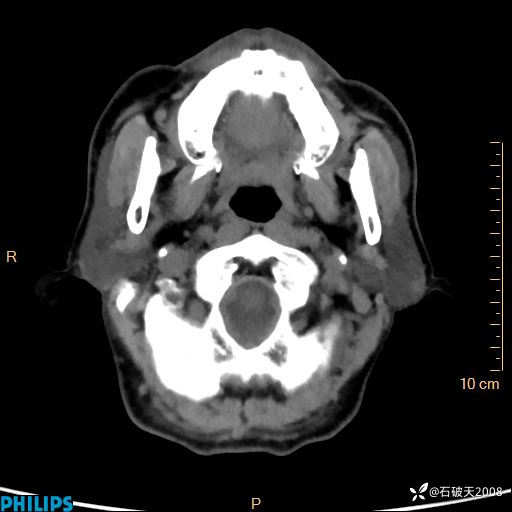

动脉期